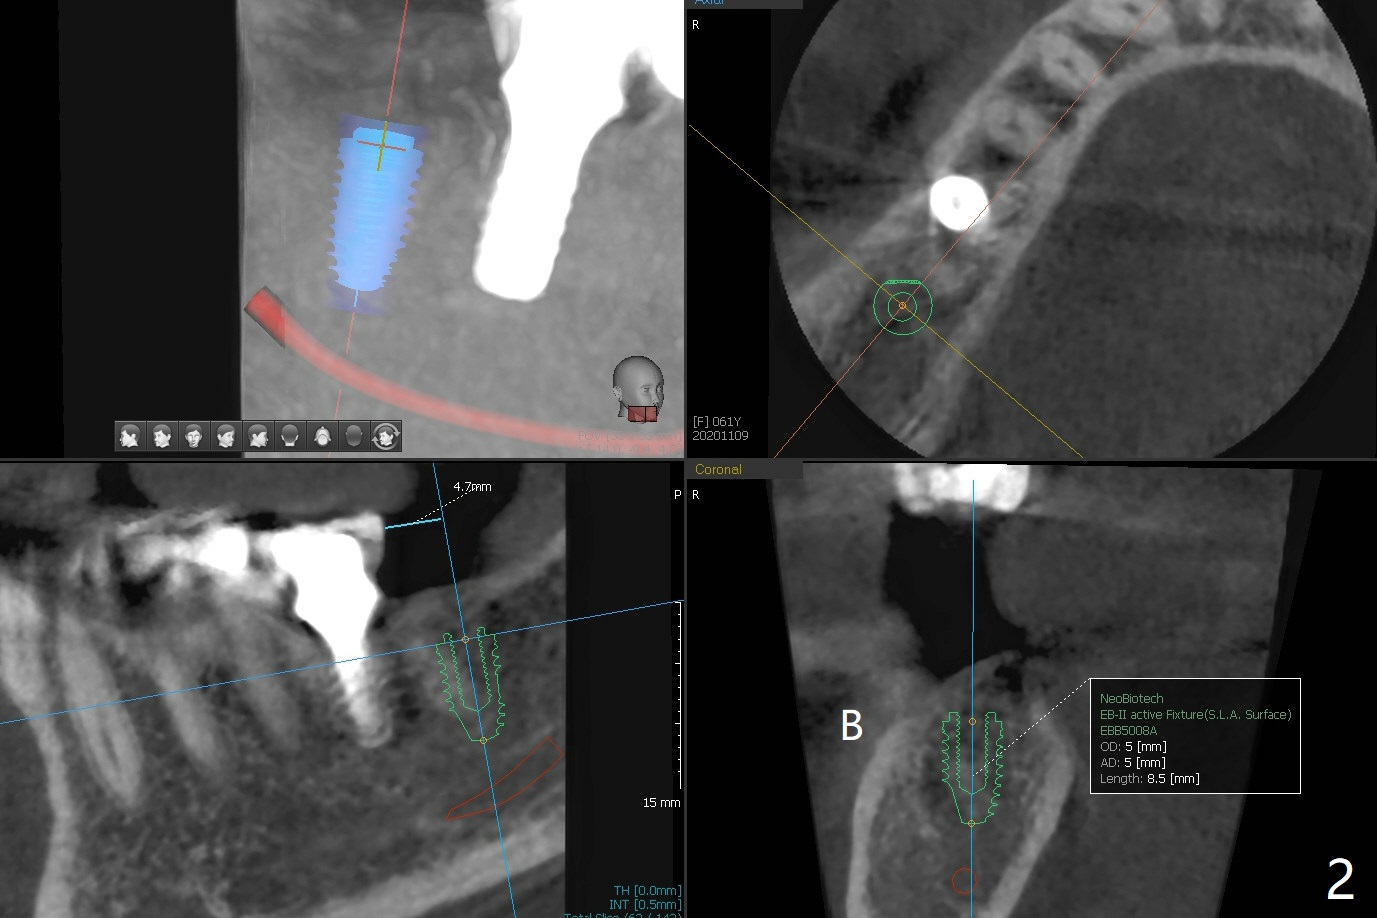

61岁女同意先做右下7植牙,可能困难是对合牙过度萌出(图一:箭头),还好对合牙牙尖比较长,有余地磨除。虽然牙槽骨很宽(图二),但是牙槽嵴顶(图三:>)缺乏皮质骨,密度很低(图四)。所以钻头必须小(4毫米),不必攻螺纹。